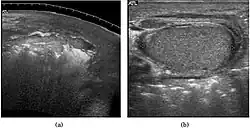

Embryonal cell carcinomas, a more aggressive tumor than seminoma usually occurs in men in their 30s. Although it is the second most common testicular tumor after seminoma, pure embryonal cell carcinoma is rare and constitutes only about 3 percent of the nonseminomatous germ cell tumors. Most of the cases occur in combination with other cell types. At ultrasound, embryonal cell carcinomas are predominantly hypoechoic lesions with ill-defined margins and an inhomogeneous echotexture. Echogenic foci due to hemorrhage, calcification, or fibrosis are commonly seen. Twenty percent of embryonal cell carcinomas have cystic components. The tumor may invade into the tunica albuginea resulting in contour distortion of the testis [Fig. 4].